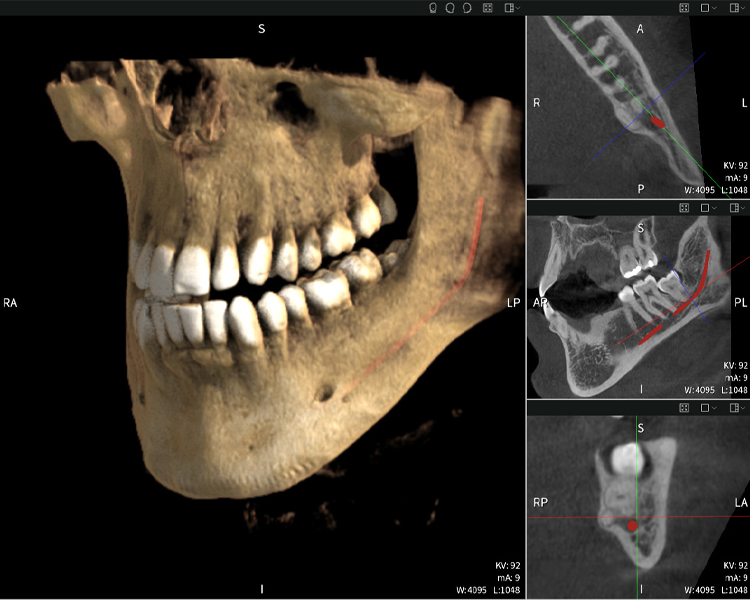

Nachstehend finden Sie einen Fall von Dr. med. dent. Oliver A. Centrella, in dem die CBCT-Aufnahmen mit Seethrough Max entscheidende Informationen zur komplexen Anatomie sowie zur kritischen Beziehung zwischen den Weisheitszähnen und dem Nervus alveolaris inferior lieferten. Bei diesem Fall besteht eine Indikation zur chirurgischen Entfernung der Weisheitszähne.

Abbildungen b–d zeigen verschiedene Ansichten einer 3D-Rekonstruktion des Unterkiefers und bieten eine umfassende Übersicht über die Anatomie des Unterkiefers, die Lage der Nerven im Verhältnis zu den Zähnen und ermöglichen die Beurteilung der Zahnsymmetrie und Ausrichtung.

Abbildung d zeigt den bereits vorbehandelten Zahn 48, dessen Krone entfernt wurde und dessen Wurzeln nahe am Nerv belassen wurden, was das hohe Risiko einer Nervenschädigung verdeutlicht.